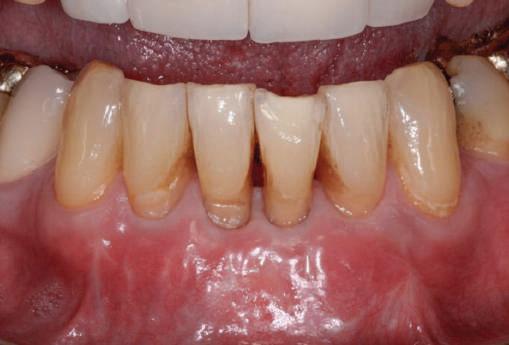

Minimizing Shrinkage of Interdental Papilla Height when Treating Multiple Miller Class III Gingival Recession Defects by Douglas H. Mahn, DDS. Originally published in Compendium of Continuing Education in Dentistry 36(4) April 2015. Copyright © 2015 to AEGIS Communications. All rights reserved.

n 1985 s-a publicat clasificarea Miller a recesiei ţesutului marginal în cadrul căreia au fost descrise patru categorii de defecte gingivale. Factorul limitant ce ghida gradul de acoperire a rădăcinii care s-ar fi aşteptat din partea oricărei proceduri de grefare era reprezentat de înălţimea papilei adiacente. Defectele de recesie gingivală de clasele III şi IV au o pierdere de os interdentar şi de ţesut moale ce limitează acoperirea rădăcinii. Papila interdentară constă din ţesut

Defectele de recesie gingivală clasa III şi IV Miller prezintă pierdere osoasă şi de ţesut moale care limitează acoperirea rădăcinii. Dată fiind importanţa papilei interdentare, ar părea o măsură prudentă protejarea integrităţii acestei structuri. Tehnicile prin tunelizare sunt utilizate cu succes în scopul protejării papilei interdentare.

conjunctiv dens acoperit de epiteliu. Tarnow şi colab. au constatat corelaţie între distanţa verticală dintre punctul de contact interdentar şi creasta osoasă şi prezenţa unei papile interdentare ce umple spaţiul ambrazurii. Având în vedere importanţa acestei structuri, Nordland & Tarnow au propus un sistem de clasificare pentru pierderea înălţimii papilare.